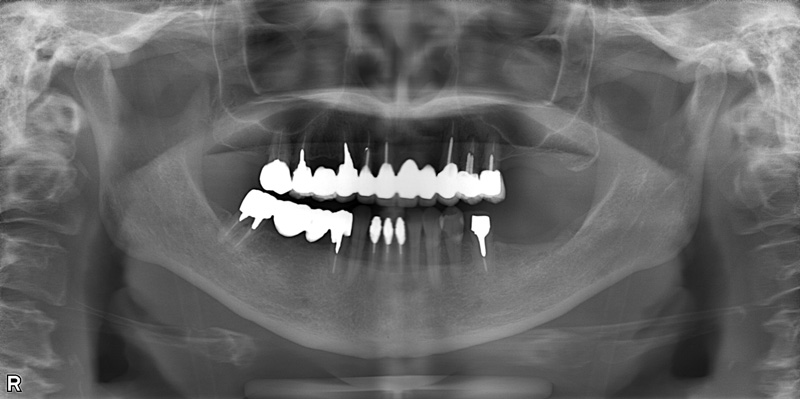

57歳男性

治療後

| 施術名 | インプラント治療 |

| 施術の説明 | インプラント治療とは、歯を抜いた所にチタン製の人工歯根を埋入し、新しく歯を入れる方法です。 |

| 施術の副作用 (リスク) | 腫れや疼痛を感じる、違和感を感じるなどの症状を生じることがあります。 |

| 施術の価格 | 53万円~+消費税 |